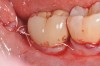

Pretreatment radiograph of a peri-implantitis

lesion on a 51-year-old male patient with a noncontributory medical history. The implant had been placed 3 years prior and presented with 8 mm pocketing with purulence.

Figure 1